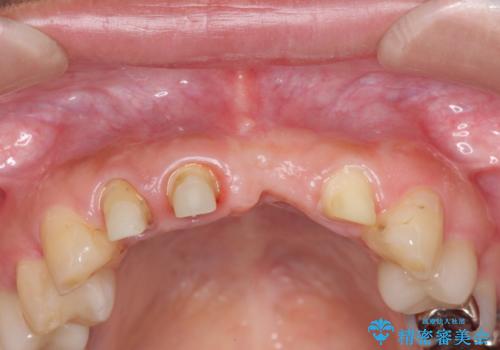

左側の前歯には他院で埋入されたポジションの悪いインプラント補綴により歯冠長の長いクラウンが装着されており、感染による排膿も認められこのまま審美性を改善するのは難しい状態です。

不良インプラントを除去し最終的にブリッジによる補綴で審美性の改善を行うこと、その準備として骨の造成・歯肉の移植による歯の欠損部顎堤のボリュームを維持・増大を計画します。

感染したインプラントからは排膿が間欠的に認められ、掻爬・除去が検討されうるような状況でした。

より審美的な改善を強く求められたため、インプラントを除去し可及的に欠損部顎堤を増大したのちブリッジによる審美改善を行いました。